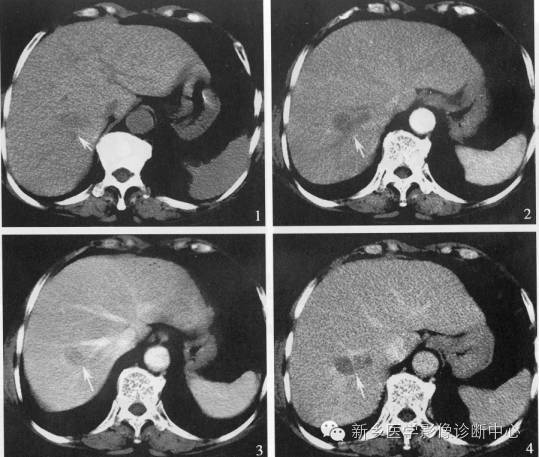

12、肝硬化再生结节

平扫多表现为高密度,增强扫描不同程度强化,延时扫描呈等密度。

小结节的RN 在螺旋CT 的平扫及动态增强扫描中常不能发现, 因为肝实质的密度都较均匀。少数大结节的RN 在增强扫描中可见, 表现为平衡期呈略低密度, 而更少数的较大的RN 在增强扫描的三期中均呈略低密度, 类似于少血供的HCC。

肝硬化结节的病理:肝细胞大量坏死,肝细胞肥大再生而形成肝硬化结节,同时伴有肝内广泛纤维化致肝小叶结构紊乱,从而导致肝脏收缩、体积缩小及肝脏表面高低不平。纤维化,结节再生,变性坏死和脂肪变性等病理改变致肝脏密度的高低不均。病理上分为3型,直径大于3cm的为大结节型,最大可达12cm,直径位于1~3cm为小结节型,二者混存为混合型;有研究表明,肝硬化再生结节以门脉供血为主,缺乏动脉供血。

肝硬化再生结节平扫一般为等密度或高密度;注射造影剂后动脉期强化不明显,在门脉期及延迟期肝硬化再生结节与肝实质密度趋向一致,这是诊断肝硬化结节的主要征象;肝硬化结节是发生在肝硬化基础上的良性增生结节,肝硬化,脾大,腹水,脾、门静脉迂曲也是诊断肝硬化再生结节的一个征象。肝脏的密度由平扫时的不均匀变为增强后的均匀,这都是诊断肝硬化结节的重要征象。

需与肝癌鉴别,肝癌平扫绝大多数呈低密度,少数呈等密度或高密度,肝癌瘤灶内的密度更低区有其多数性,多形性及多层面显示的特征;肿瘤边缘的“晕圈征”和CT平扫边缘不清而常规增强后缘变清楚且肿瘤随之变小及周围的“卫星”结节直径3~5cm时,其动脉期强化一般是不均匀的,极少数是均匀的;增强过程癌结节造影剂的充盈呈“快进快出”的表现。值得注意的是肝癌与肝硬化结节共存时,容易漏诊。